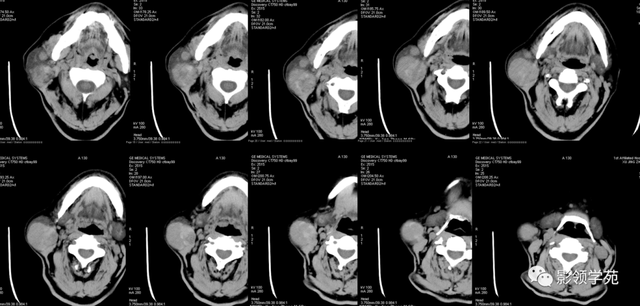

腮腺恶性肿瘤CT体现:

边缘不规则或分叶;

密度不均,可有出血、坏死、液化、囊变

与相近 结构差异水平粘连,对周围腺体呈侵蚀性体现,易向腺外结构侵占 ,使腺体与周围脂肪、肌肉组织间隙中的筋膜模糊或消逝 。

增强,不均质强化。

颈部淋投合肿大及转移征象。